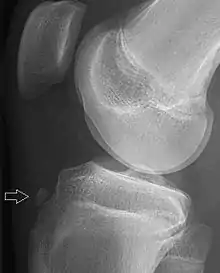

X-ray of a 15 year old male, showing an older avulsion fracture of the tibial tuberosity.

A tibial tuberosity avulsion fracture is an incomplete or complete separation of the tibial tuberosity from the tibia. This occurs as a result of a violent contraction of the quadriceps muscles, most often as a result of a high-power jump. Incomplete fractures are usually treatable with the traditional RICE (rest, ice, compression, elevation) method, but complete/displaced fractures will most often require surgery to pin the tuberosity back in place. Tibial tuberosity avulsions occur most often in teenagers that engage in a large amount of sporting activities, and many studies have shown a history with Osgood-Schlatter's disease to be linked to the fracture.